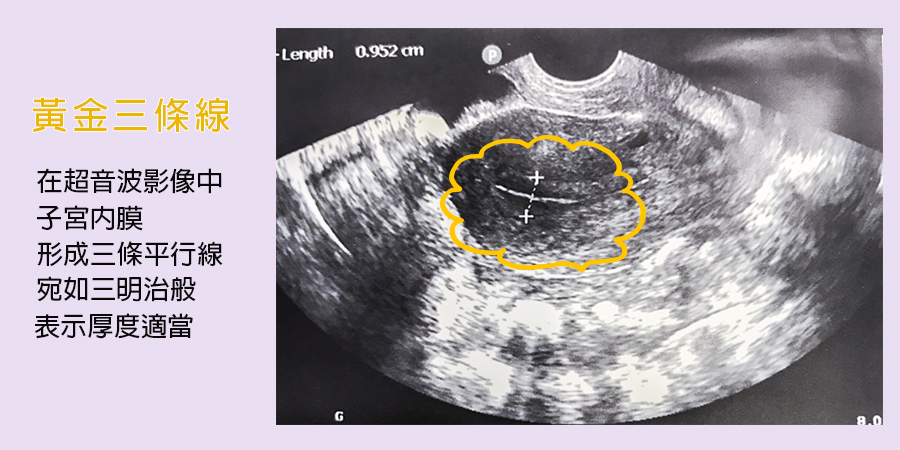

想要胚胎順利著床,內膜厚度要好、型態也要好。當女性排卵期來臨,子宮的內膜厚度增為9-10mm是最佳胚胎著床厚度;在型態上,隨著排卵期來臨,雌激素上升與卵泡的增長,內膜開始增厚,則會形成「黃金三條線」(在超音波影像下),是最佳的胚胎著床環境。